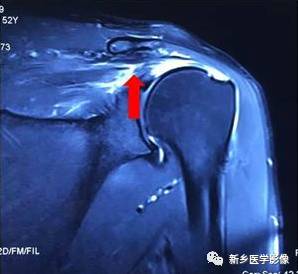

病例二:

红色箭头:冈上肌腱近止点撕裂,大小约1cm